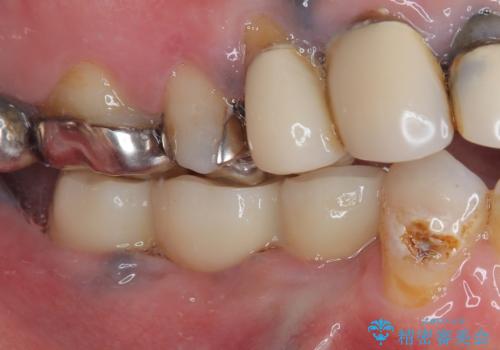

- ブリッジが装着されている奥歯がぐらぐらするとのことで来院された患者様です。

診察を行ったところ、手前の歯は歯根が破折しており、抜歯が必要な状態でした。

左右ともに臼歯部しか咬んでおらず、ブリッジの手前側の歯が破折したことで大きく揺さぶられてしまい、奥側の歯も周辺の歯が著しく吸収し、抜歯が必要な状態でした。